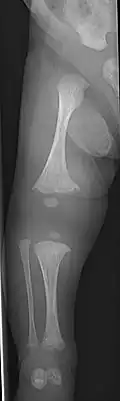

Diagnosis

Diagnosis is typically based on medical imaging, including plain X-rays, and symptoms. In severe OI, signs on medical imaging include abnormalities in all extremities and the spine.[97] As X-rays are often insensitive to the comparatively smaller bone density loss associated with type I OI, DEXA scans may be needed.[5]: 1514

An OI diagnosis can be confirmed through DNA or collagen protein analysis, but in many cases, the occurrence of bone fractures with little trauma and the presence of other clinical features such as blue sclerae are sufficient for a diagnosis. A skin biopsy can be performed to determine the structure and quantity of type I collagen. While DNA testing can confirm the diagnosis, it cannot absolutely exclude it because not all mutations causing OI are yet known and/or tested for.[83]: 491–492 OI type II is often diagnosed by ultrasound during pregnancy, where already multiple fractures and other characteristic features may be visible. Relative to control, OI cortical bone shows increased porosity, canal diameter, and connectivity in micro-computed tomography.[98] OI can also be detected before birth by using an in vitro genetic testing technique such as amniocentresis.[99]